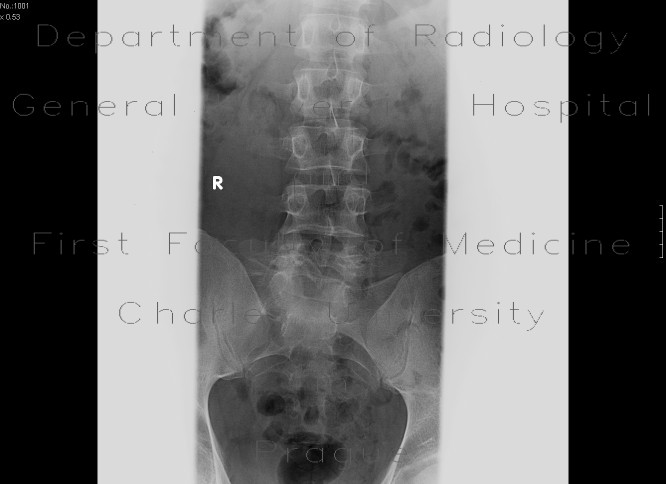

| pondylolistéza, spondylolýza, spina bifida: (statický) RTG snímek, dvě projekce | Spondylolistéza, spondylolýza, spina bifida: (statický) RTG snímek, dvě projekce |